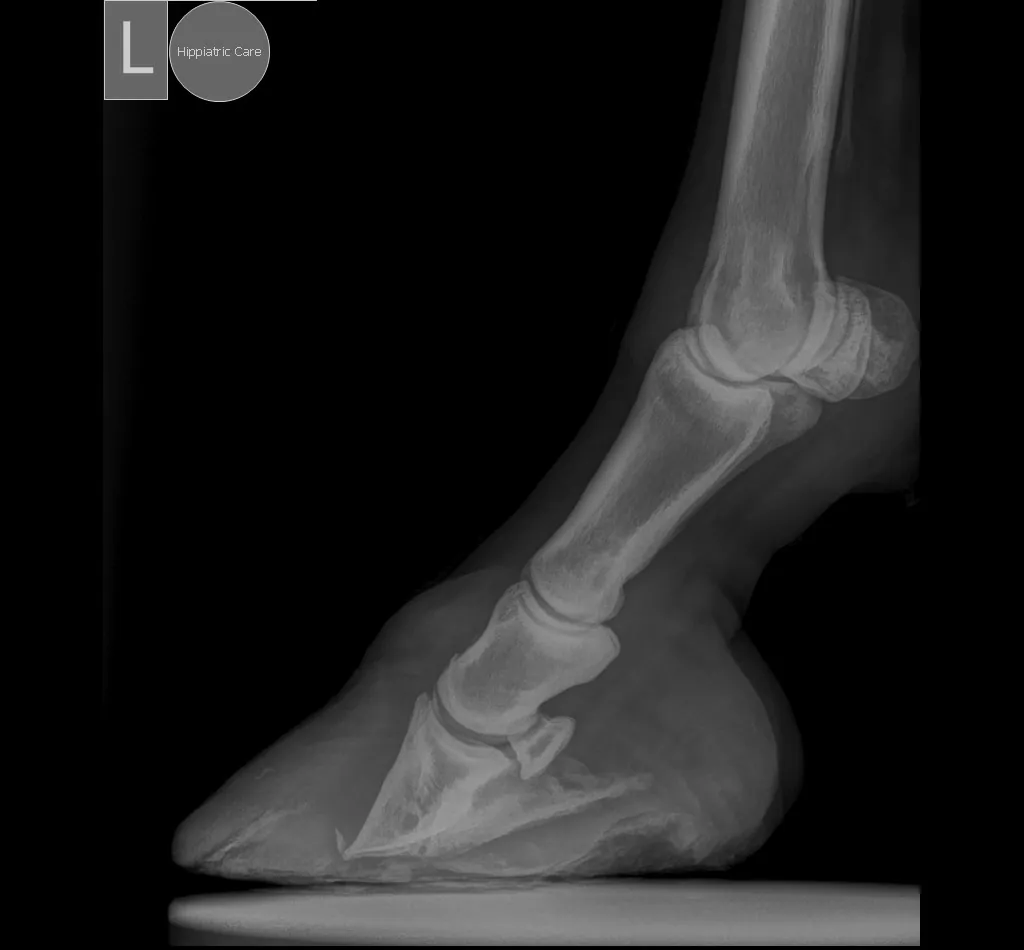

Radiography is essential to:

✓ Confirm the presence of laminitis.

✓ Determine the degree and type of distal phalanx displacement.

✓ Guide trimming and shoeing decisions.

✓ Monitor disease progression and treatment response.

Venography is a highly valuable tool for the diagnosis and treatment of laminitis, as it allows assessment of vascular damage in the hoof before changes become evident on conventional radiographs. Its value is greatest when performed at the onset of the disease, as it reveals the level of damage that has already occurred and helps guide the selection of the appropriate therapeutic strategy.

Clinical examination, radiography and laboratory testing are complementary tools, not alternatives.